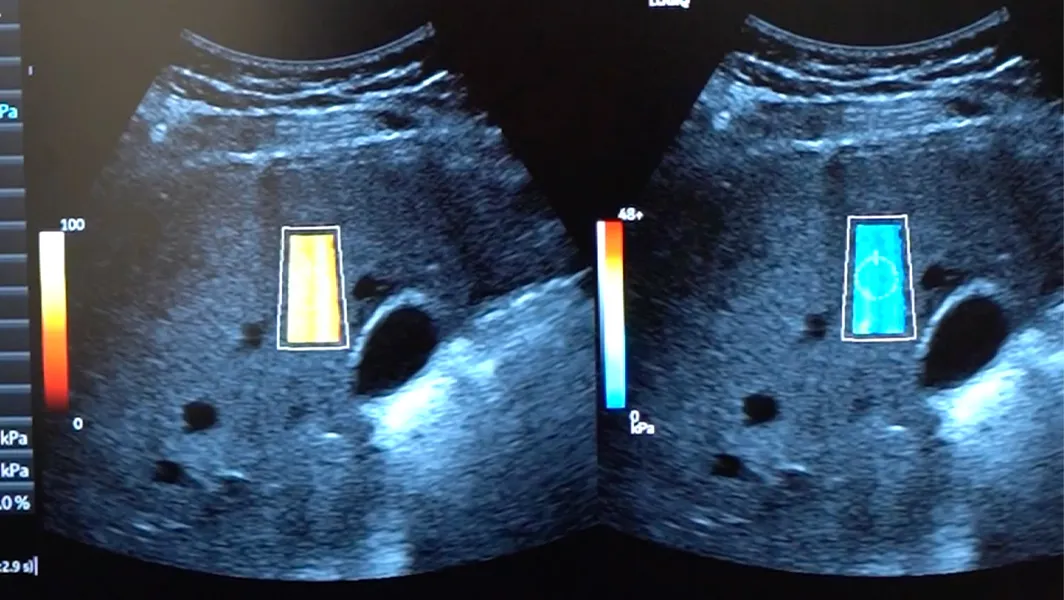

31mar.2026 Imagenología Elastografía por ultrasonido: ya contamos con examen clave para medir la salud del hígadoVer más